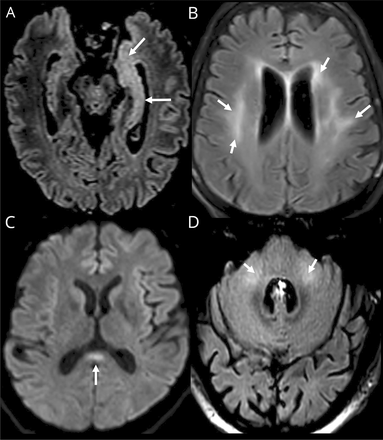

Ischemic strokes (27%) (figure e-1, available from Dryad,doi.org/10.5061/dryad.w9ghx3fm7), LME (17%) (figure 1), and encephalitis (13%) (figures 2and3and figure e-2, available from Dryad) were the most frequent neuroimaging findings. LME was seen on both postcontrast T1-weighted and FLAIR sequences and was even better visualized when delayed postcontrast FLAIR was performed. These signal abnormalities were not present on precontrast T1 or FLAIR images.

Axial T1 (A) before and (B) 5 minutes after contrast, axial FLAIR (C) before and (D) immediately after contrast, and (E and F) delayed (10 minutes) postcontrast axial fluid-attenuated inversion recovery (FLAIR) weighted MRIs. Woman 77 years of age: diffuse leptomeningeal linear FLAIR and T1 contrast enhancement (arrows) not visible on precontrast T1 and FLAIR (arrows) but seen better on delayed postcontrast FLAIR weighted MRIs (E and F).